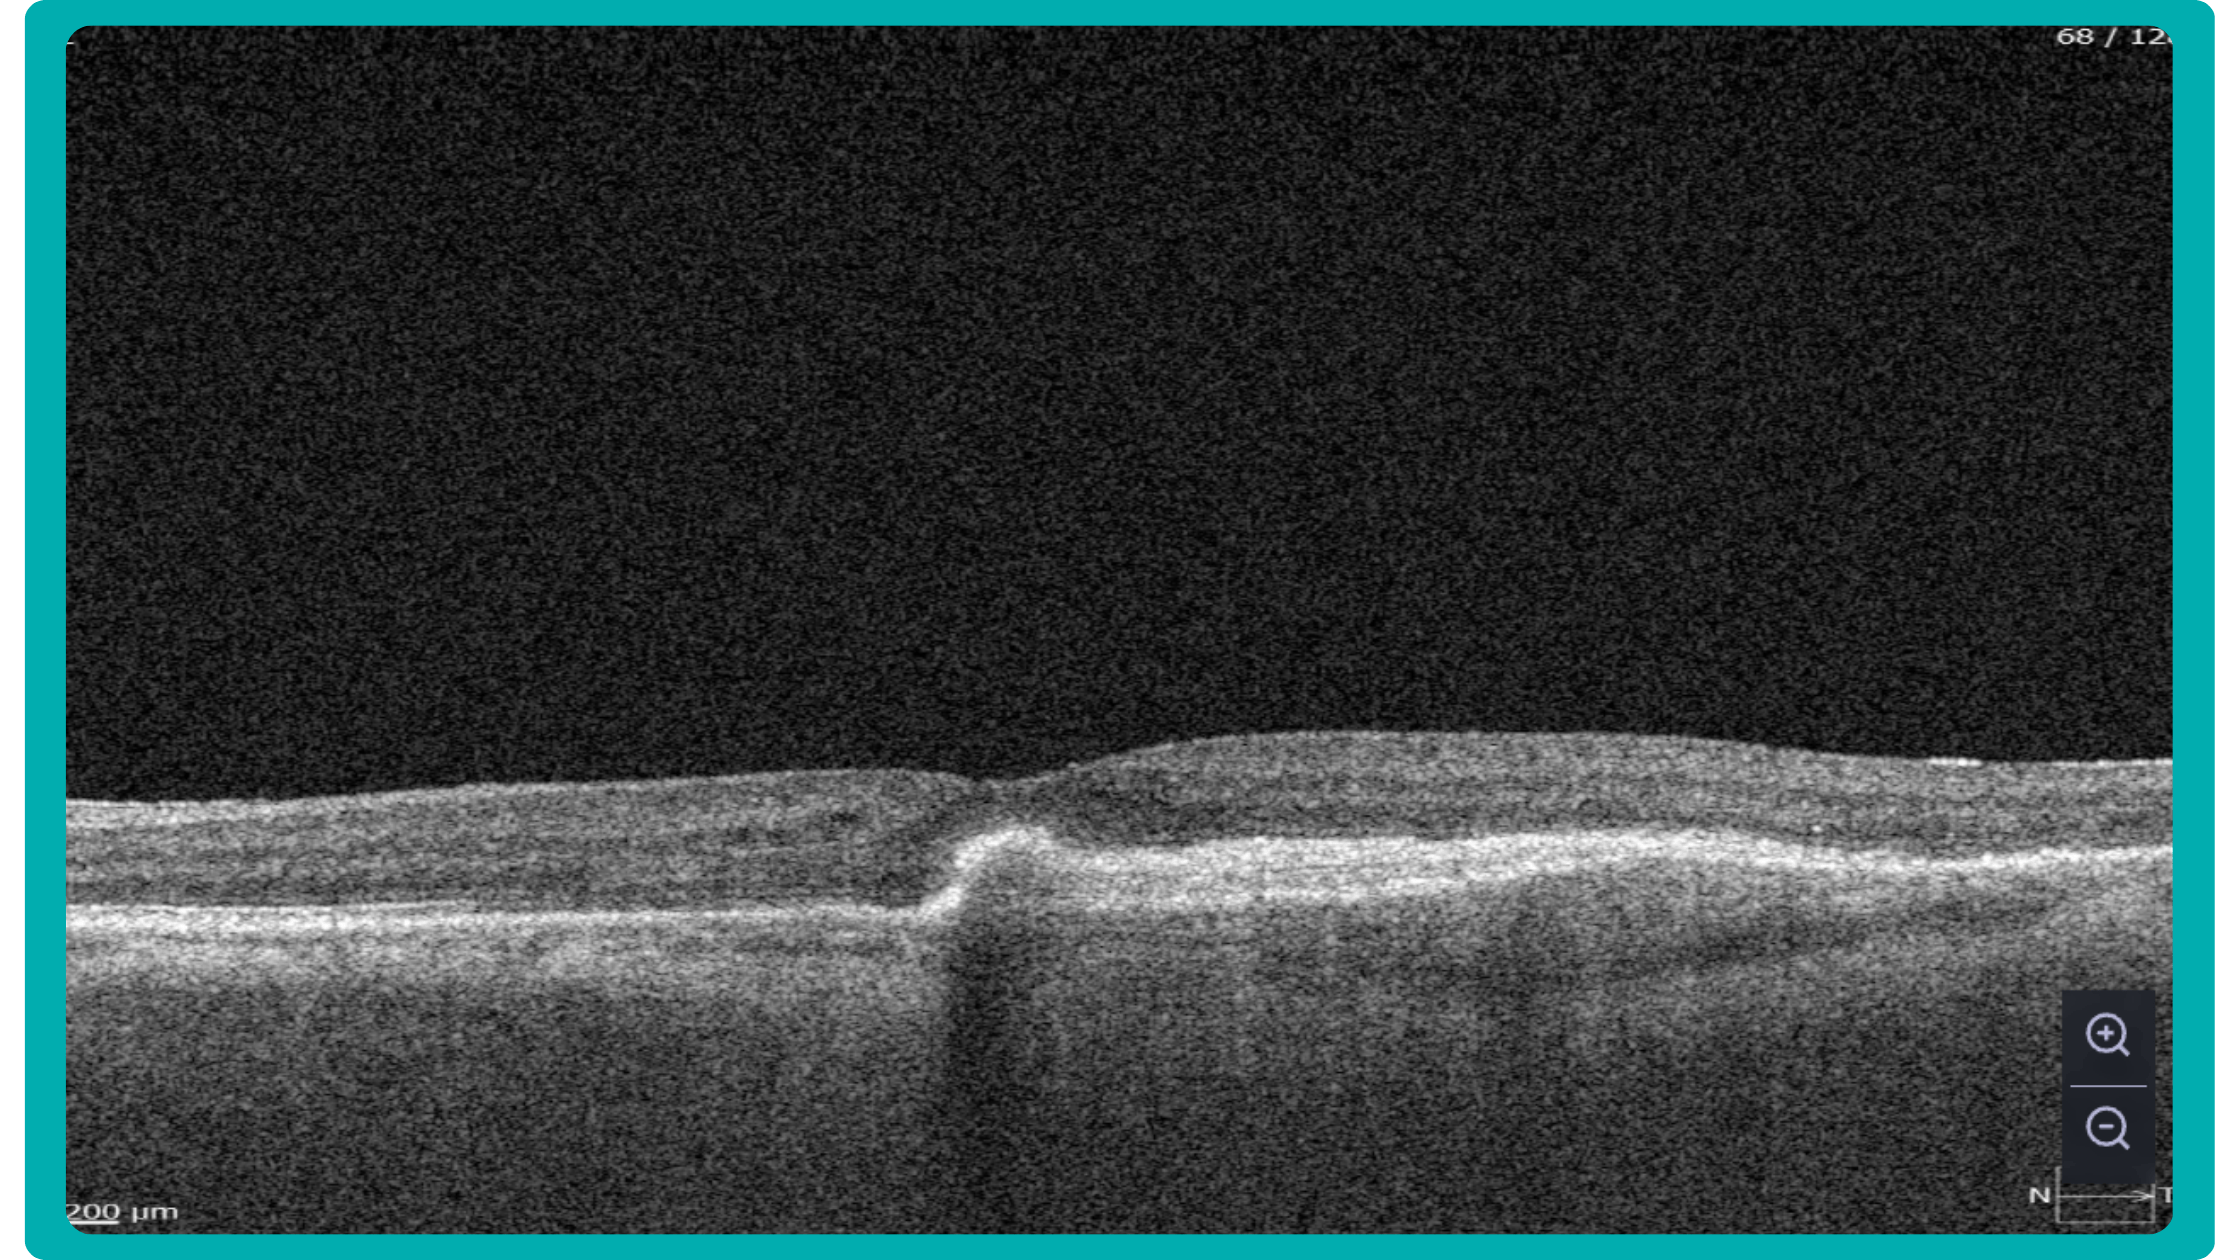

While retinal reports vary among OCT models, they typically include:- a foveally centered B-scan,

The B-scan offers a visual snapshot of foveal architecture and confirms proper scan centering. The quantitative thickness map employs the ETDRS sector map to measure retinal thickness within a 6mm circle around the fovea, with specific measurements for the foveal sector (1mm), inner macular ring (3mm), and outer macular ring (6mm).

Let’s explore how this applies to a clinical case, such as monitoring a patient with Wet AMD during follow-up visits.

Data demonstrates that OCT findings can reveal the onset or progression of neovascular AMD before a patient reports new symptoms or changes in visual acuity. In fact, OCT images are reported to have the best diagnostic accuracy in monitoring nAMD disease states. This underscores the importance of key OCT findings or biomarkers in personalizing anti-VEGF treatment, achieving disease control, and reducing monitoring burdens.

Central Retinal Thickness emerged as one of the earliest OCT biomarkers used as an outcome measure in clinical trials for nAMD.

Another finding that is correlated with a worsening VA due to the associated photoreceptor defects is any damage to the four outer retina layers, including the RPE, interdigitation zone (IZ), ellipsoid zone (EZ), and external limiting membrane band (ELM).

OCT is a valuable imaging tool for visualizing subretinal hyperreflective material (SHRM). It can automatically identify and quantify SHRM and fluid and pigment epithelial detachment to calculate the overall risk of worsening visual outcomes associated with SHRM.

Subsequent follow-up visits will then display the most relevant picture, highlighting the most pertinent biomarkers for tracking a particular pathology (wet AMD in our example) and comparing their volume, progression, or regression through visits.

Another helpful option is retinal layer segmentation, which focuses solely on the retinal layers of interest for the specific case.

This level of customization empowers clinicians with a comprehensive yet targeted view of the patient’s condition. It saves time from manually detecting anomalies on scans and facilitates informed decision-making and personalized treatment plans.

In ophthalmology, AI-powered analysis of OCT scans can provide precise, quantitative measurements of retinal thickness, fluid volume, and other biomarkers relevant to diseases like diabetic retinopathy and age-related macular degeneration. These measurements can aid in diagnosis, disease staging, treatment monitoring, and prediction of treatment response.

Systems like Altris for pathology detection and segmentation enabled automated disease characterization and longitudinal monitoring of therapeutic response in AMD. Multiple studies have demonstrated the value of volumetric fluid characterization, compartment-specific OCT feature evaluation, and subretinal fibrosis and hyperreflective material quantification.

The extraction of quantitative fluid features and assessment of retinal multi-layer segmentation from OCT scans have offered valuable insights into disease prognosis and longitudinal dynamics of Diabetic Retinopathy.

A recent study demonstrated that quantitative improvement in ellipsoid zone integrity following anti-VEGF therapy for DME significantly correlated with visual function recovery. Furthermore, novel imaging biomarkers, such as the retinal fluid index (RFI), are emerging as tools for precisely monitoring treatment response. Studies have shown that early RFI volatility can predict long-term instability in visual outcomes after treatment.